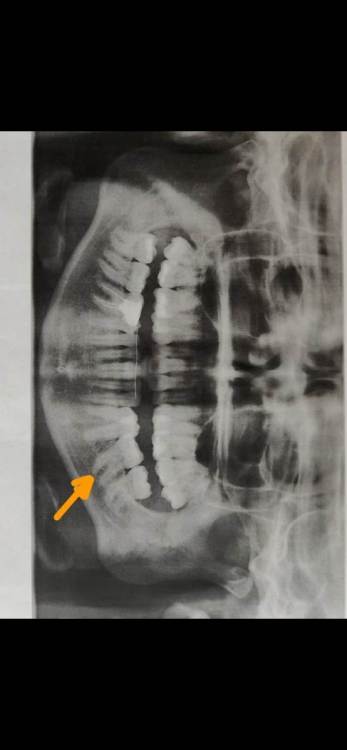

gomyranchik Опубликовано 31 декабря, 2021 Поделиться Опубликовано 31 декабря, 2021 Добрый день! 1) Могут ли элайнеры изменить наклон корней моляра? (на рентгеновском снимке видно, как корни одного из моляров сильно отклонены) 2) Стоит ли в моем случае вообще исправлять данный наклон? Насколько это критично, может ли быть негативное влияние в будущем, если оставить всё, как есть? Мне 33, живу с этим всю жизнь. Проходила лечение брекетами 11 лет назад, но мне тогда этот зуб не трогали. 3) Подскажите, пожалуйста, насколько реализуем данный план лечения с помощью инвизилайн (ссылка и доступ ниже)?https://share.invisalign.com/treatment-viewer/latest/index.html#/welcome?shareId=f24fef88-c45c-43f0-a76c-6c4690014908&shareThrough=PATIENT Пароль для входа: **** Заранее большое спасибо! Ссылка на комментарий

АнтонТЛТ Опубликовано 1 января, 2022 Поделиться Опубликовано 1 января, 2022 Добрый день, такой наклон вполне реализуем на элайнерах без применения дополнительных опор. Ортодонтическое лечение Вам показано. Ваш план лечения выглядит незаконченным. Ссылка на комментарий

АнтонТЛТ Опубликовано 5 января, 2022 Поделиться Опубликовано 5 января, 2022 Задние бугры верхнего левого первого моляра находятся ниже уровня где они должны быть, это связано с выдвижением зуба из-за длительного наклона нижнего левого первого моляра. Так же этот верхний зуб находится в более нёбном положении относительно соседних зубов. Ссылка на комментарий

АнтонТЛТ Опубликовано 5 января, 2022 Поделиться Опубликовано 5 января, 2022 Правый верхний первый моляр так же имеет наклон задних бугров, связано это скорее всего с тем, что нижний правый первый моляр долго находился в разрушенном состоянии и верхний зуб выдвинулся. Нужно поменять наклон верхнего зуба и потом сделать коронку на нижнем. Ссылка на комментарий

АнтонТЛТ Опубликовано 5 января, 2022 Поделиться Опубликовано 5 января, 2022 Эти выдвинувшиеся верхние зубы создают блок в движении нижней челюсти. Из-за этого блока нижняя челюсть движется по неправильной траектории и смещается в сторону. Что в дальнейшем может привести к проблемам в височно- нижнечелюстных суставах. Перед ортодонтическим лечением нужно удалить зубы мудрости и вылечить все зубы где есть кариес. Так же разобраться с нижним правым первым моляром, если там есть проблемы с корнями. 1 Ссылка на комментарий